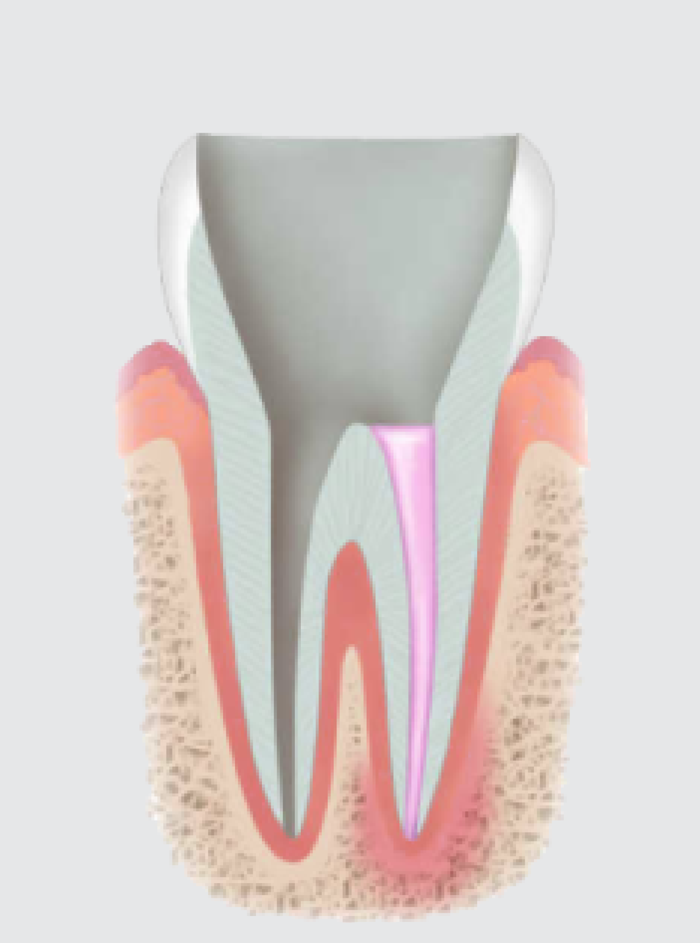

신경치료 과정

충치가 심해서 신경치료를 하게 되는 경우 먼저 치아의 충치를 모두 제거하고 치수까지 구멍을 뚫습니다. 이 공간을 통해서 치아의 뿌리 부위까지 안 쪽에 있는 치수(신경 조직)을 모두 제거하고 일정한 크기로 확대시킨 후 치과용 생체 적합 재료로 채워 넣습니다. 신경치료를 마친 치아는 약해져서 부러지기 쉽기 때문에 크라운 치료를 해줘야 합니다.

• STEP 01

심한 충치로 인해 신경조직이 감염되어 신경치료가 필요한 상태입니다.

• STEP 02

치아 겉면의 충치와 염증이 생긴 내부의 신경조직을 제거합니다.

• STEP 03

깨끗이 제거된 내부의 신경관을 소독한 후 충전 재료로 채웁니다.

• STEP 04

신경치료 후 손상되기 쉬운 치아를 보호하기 위해 크라운을 씌웁니다.